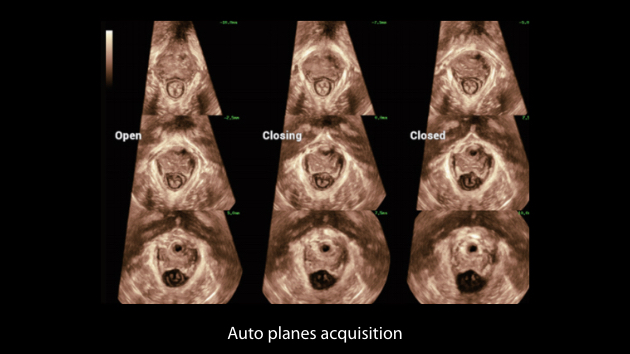

Nuewa I9, kad?nlara ve yenido?anlara y?nelik sa?l?k hizmetleri i?in ?zel olarak tasarlam??t?r ve i?ten d??a yenilik?i bir deneyim sunmaktad?r. Bu yenilikler, karma??k klinik senaryolara ili?kin derinlemesine bilgilere dayal? olarak geli?tirilmi?tir ayr?ca do?ru ve zaman?nda yan?tlar?n yan? s?ra, ola?an├╝st├╝ verimlilik ve ola?an├╝st├╝ kullan?c? deneyimi sunar.